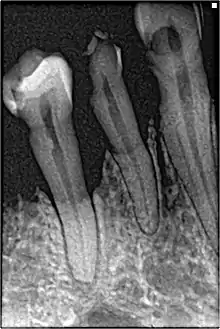

Perhaps the most serious oral condition that can arise is that of oral cancer. However, smoking also increases the risk for various other oral diseases, some almost completely exclusive to tobacco users. The National Institutes of Health, through the National Cancer Institute, determined in 1998 that "cigar smoking causes a variety of cancers including cancers of the oral cavity (lip, tongue, mouth, throat), esophagus, larynx, and lung."[102] Pipe smoking involves significant health risks,[110][111] particularly oral cancer.[112] Roughly half of periodontitis or inflammation around the teeth cases are attributed to current or former smoking. Smokeless tobacco causes gingival recession and white mucosal lesions. Up to 90% of periodontitis patients who are not helped by common modes of treatment are smokers. Smokers have significantly greater loss of bone height than nonsmokers, and the trend can be extended to pipe smokers to have more bone loss than nonsmokers.[113]

Smoking has been proven to be an important factor in the staining of teeth.[114][115] Halitosis or bad breath is common among tobacco smokers.[116] Tooth loss has been shown to be 2[117] to 3 times[118] higher in smokers than in non-smokers.[119] In addition, complications may further include leukoplakia, the adherent white plaques or patches on the mucous membranes of the oral cavity, including the tongue.[120]